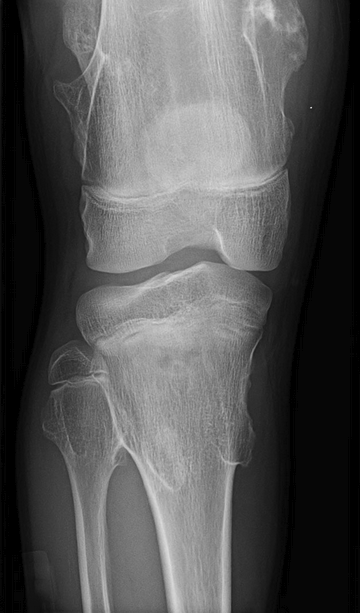

14 y/o boy, knee pain after tripping and falling on wrestling mat

fixed, hard lesions palpated above and below the knee; cortices are contiguous with cortex of surrounding bone

osteochondroma